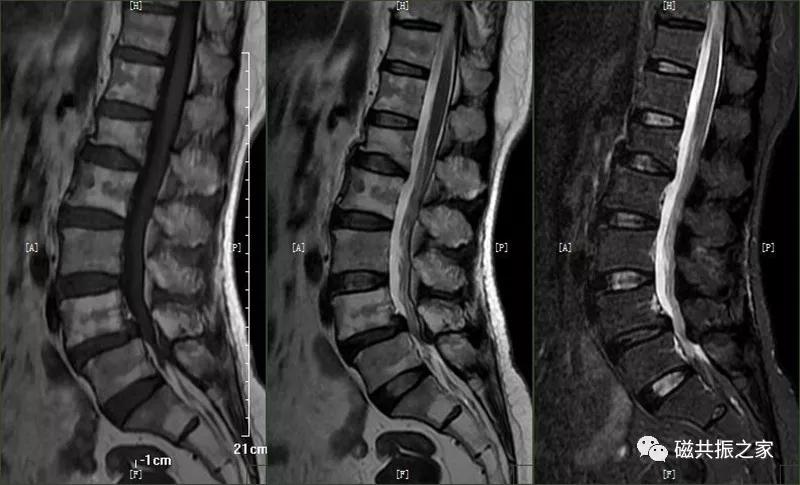

10.椎体肿瘤

椎体常见的肿瘤为转移瘤

椎体转移瘤T1WI常表现为低信号,T2WI为高/中/低信号,脂肪抑制为高信号,常累及附件。

疑是血液系统疾病引起的腰椎异常信号改变,部分炎性病变可引起该表现。